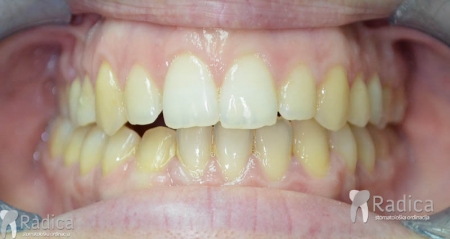

U sljedećem primjeru su se na mjesto donjih ekstrahiranih prvih molara stavili dentalni implantati prije ortodontske terapije (rad dr. Gorana Radice) i ujedino su služili za pojačenje sidrišta tijekom ortodontske terapije. Nakon ortodontske terapije estetski su se preoblikovali sjekutići i napravile nove krunice (također rad dr. Gorana Radice).